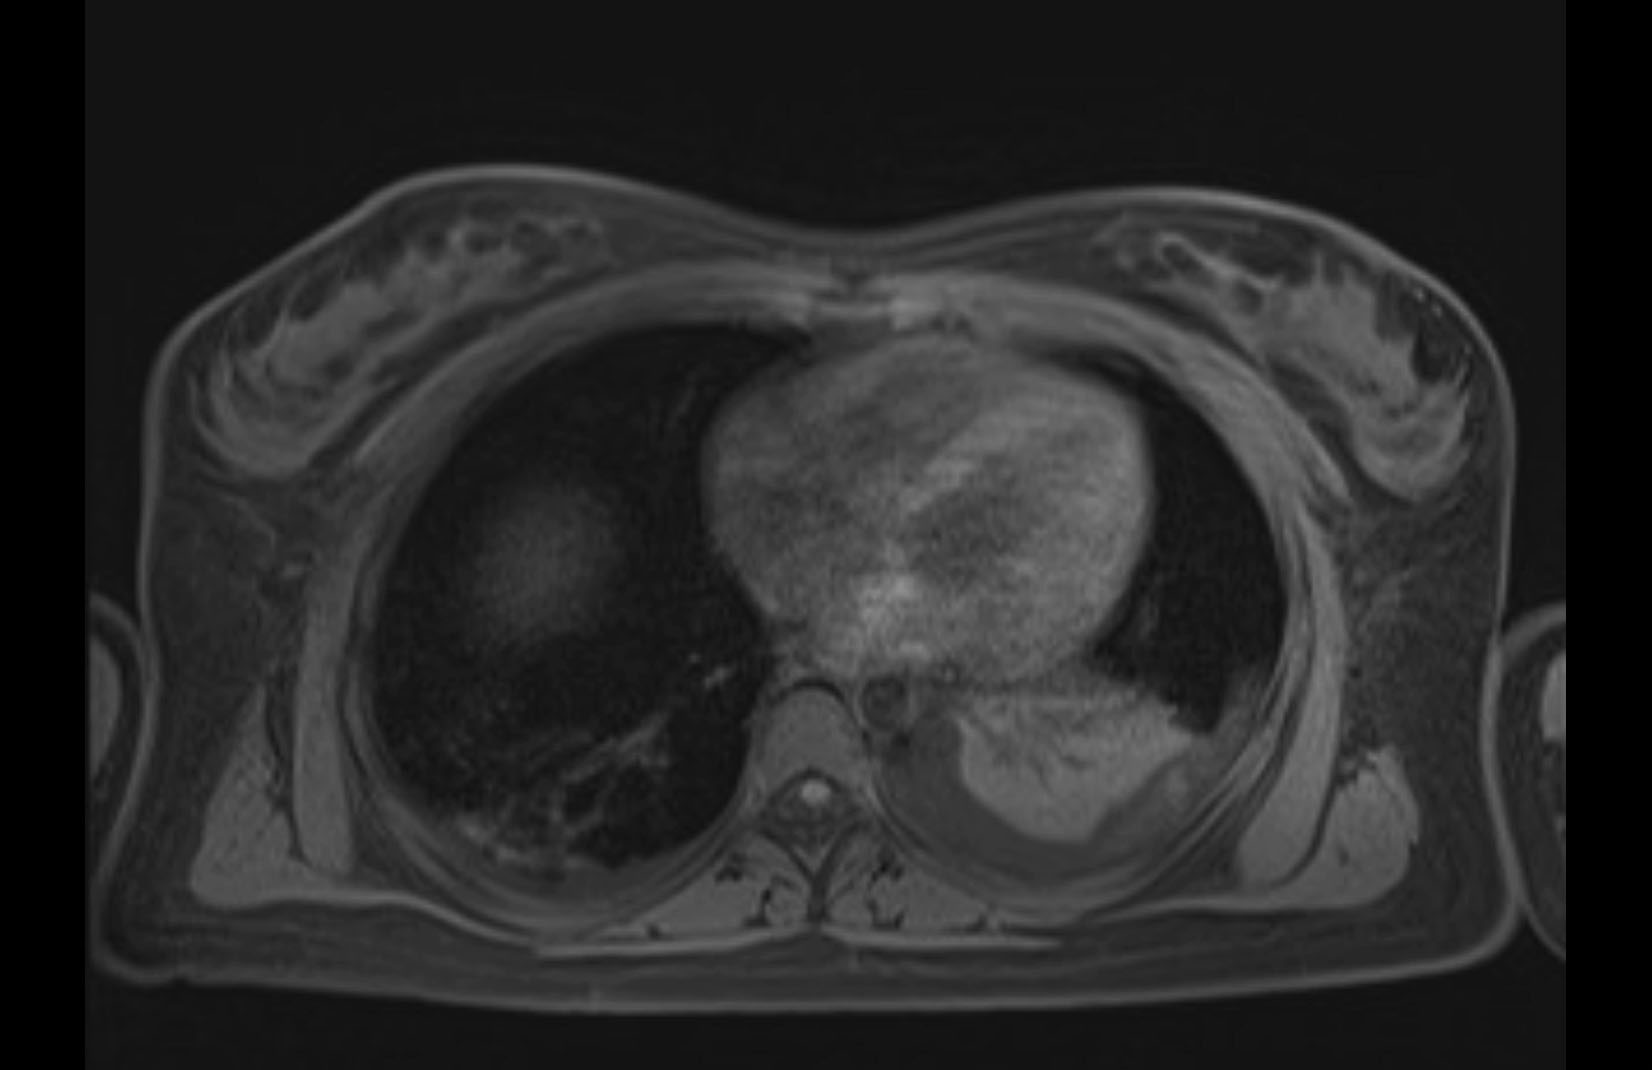

Imaging Analysis

Look through the patient's CT scan to identify any areas of concern for the necessary procedure.

MRI T2

Based on initial findings, which issue(s) would you be most concerned about?